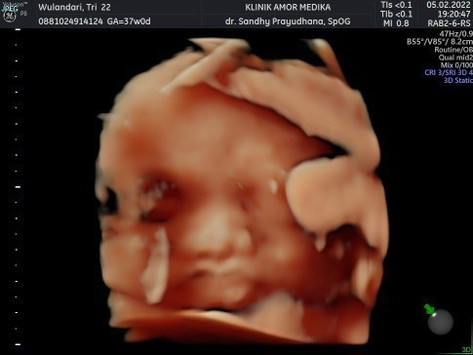

Assalamu'alaikum bunda-bunda.. Mau sharing bunn sekalian minta sarannya,soalnya aku kepikiran bgt Bun janin ku 37w BB-nya cuma 2,5g tiap pagi juga masih suka mual kadang sampe muntah Bun trs BB awal aku juga kecil cuma 37kg ,cara cepet naikin BB janin selain makan daging merah apalagi ya bunn? #pleasehelp #firstbaby #bantusharing #seriusnanya